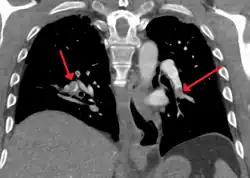

On CT scan, pulmonary emboli can be classified according to level along the arterial tree. -

Segmental and subsegmental pulmonary emboli on both sides -

CT pulmonary angiography showing a "saddle embolus" at the bifurcation of the main pulmonary artery and thrombus burden in the lobar arteries on both sides.